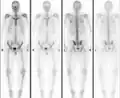

Osteopoikilosis

Normal bone scan in a person with osteopoikilosis